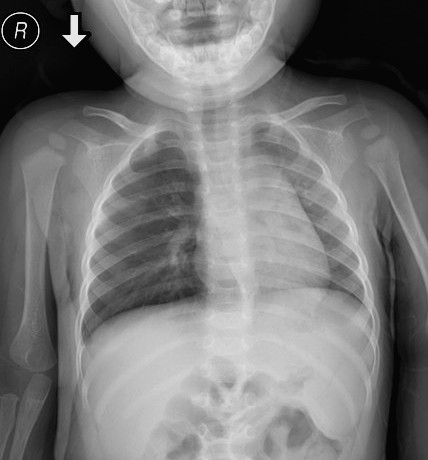

患儿男,2岁,临床以支气异物送来拍仰卧位胸片。有结果,暂时不告知患者异物吸入史。

仅凭这张平片(这个患儿没做CT),你的诊断是什么?异物在哪侧支气管呢?为什么?